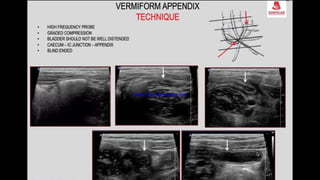

This document discusses the evaluation of right lower abdominal pain and lists appendicitis as a key cause. It notes that other potential causes include hemorrhagic cysts, heterotrophic pregnancy, salpingitis with pyosalpinx, funiculitis, and torsion of an undescended testis. The document was presented by Dr. A.S.M. Sufian of Cumilla Medical College Hospital and thanks the audience for their patience and listening.